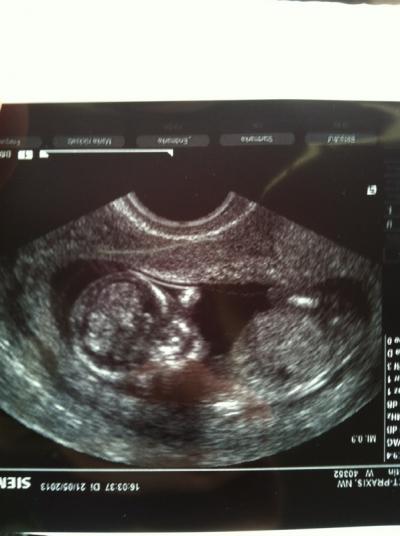

Hallo ihr, bin jetzt 12+4, das Baby ist ca 5,5cm groß. Schon ganz schön gewachsen. Sieht alles soweit gut aus, meine Tochter (9J.) war dabei, der kleine Zwerg hat die ganze Zeit geschlafen, die FÄ hat ihr alles ganz süß erklärt. Dann hat sie gefragt, ob sie es mal wecken soll. Sie hat es dann kurz angeschupst und das kleine ist total erschrocken und hat gezappelt. Meine Tochter musste richtig lachen, sie fand das total süß, glaub sie will jetzt immer mit zum US. Leider hab ich in 4 Wochen nur normale Vorsorge und in 6 Wochen erst wieder US. Könnte jedesmal US für 100€ machen lassen, muss ich mir mal überlegen. Das Bild hat sie extra für meine Tochter gemacht, sie sagte es streckt ihr schon die Zunge raus

Bild zu zurück vom FA... - Forum für November - Mamis